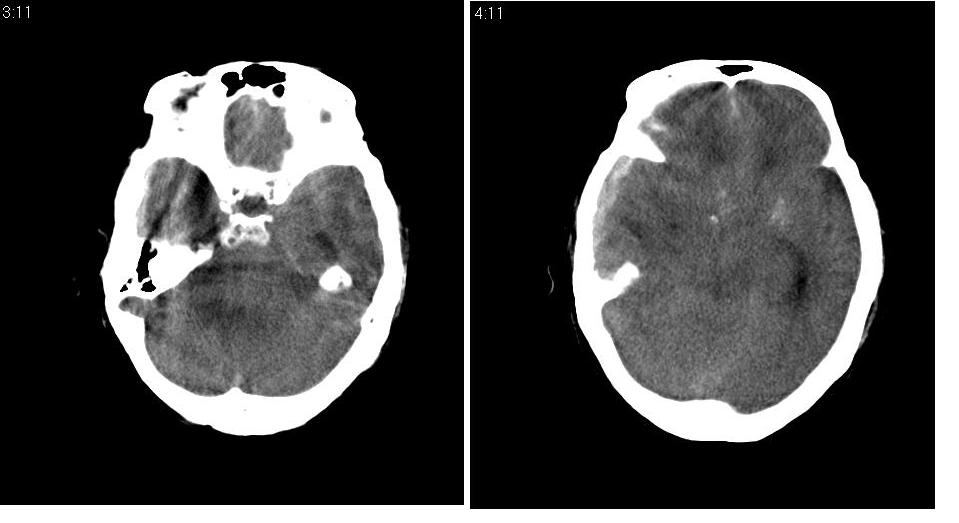

以下是引用川北影像在2007-8-14 15:33:00的发言:[br]1、右侧颞叶脑挫裂伤伴血肿形成。[br]2、右侧额颞顶部硬膜下血肿伴大脑廉下疝形成。

以下是引用gaoshengjiang在2007-8-14 16:30:00的发言:[br]大家都认为右侧颞叶脑挫裂伤伴血肿形成;右侧额颞顶部硬膜下血肿伴大脑廉下疝形成;蛛网膜下腔出血。 但硬膜下血肿、脑内血肿量不多,而大脑廉下疝明显,右侧颞叶类圆形高密度灶,周围轻度水肿,呈蟹足状,考虑脑内占位所致脑内血肿、突然晕倒、硬膜下血肿、颞叶脑挫裂伤等一系列改变。[br][br] [br]

以下是引用拾荒者在2007-8-14 21:59:00的发言:[br][quote]以下是引用gaoshengjiang在2007-8-14 16:30:00的发言:[br]大家都认为右侧颞叶脑挫裂伤伴血肿形成;右侧额颞顶部硬膜下血肿伴大脑廉下疝形成;蛛网膜下腔出血。 但硬膜下血肿、脑内血肿量不多,而大脑廉下疝明显,右侧颞叶类圆形高密度灶,周围轻度水肿,呈蟹足状,考虑脑内占位所致脑内血肿、突然晕倒、硬膜下血肿、颞叶脑挫裂伤等一系列改变。[br][br] [br]